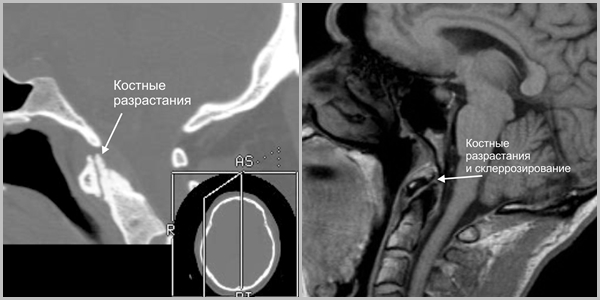

- В головах и верхнешейном отделе позвоночника выявляется картина артроза Крювелье: краевые разрастания суставных поверхностей сустава.